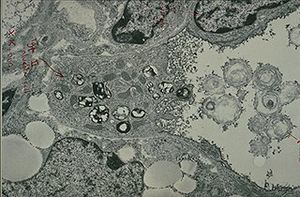

تتم عملية انتاج هذه البروتينات في الخلايا السنخية من النمط الثاني ، تنتقل هذه الخلية من حيث تنتج إلى الجسم العديد الصفاحات و هي حلقات دائرية تتكون من شحوم (دهون) و بروتينات قطرها 0.000001 متر (1 ميكرو متر).

الإنتاج

تحدث عملية انتاج فاعل بالسطح الرئوي في الخلايا السنخية من النمط الثاني خلال مرحلة محطة الحوصلة أثناء تطور الرئنين ، تظهر الأجسام العديدة الصفاحات في السيتوبلازم بعد 20 أسبوع من الحمل ، تخرج هذه الأجسام من الخلايا السنخية من النمط الثاني عن طريق عملية الإيماس (هي عملية تخرج فيها الخلية الأجسام الى خارج غشائها) ثم تنتقل الى الطبقة المائية التي تغطي الأسناخ الرئوية أي في الموقع الذي يشكل فاعل بالسطح الرئوي أنيبيبات من الميالين التي تخزن في الجسم العديد الصفاحات .